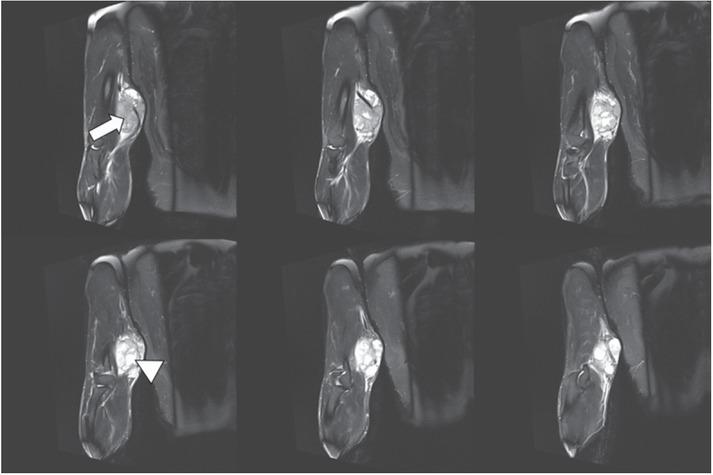

Figure 2

1.5-T MRI of the arm (proton density [PD] fat saturation [FS]: 6 consecutive slices of 3 mm) of a 54-year-old patient. The higher-grade polycyclic/multilobulated sarcoma in the upper arms shows solid (white arrow) and cystic (white arrowhead) components.